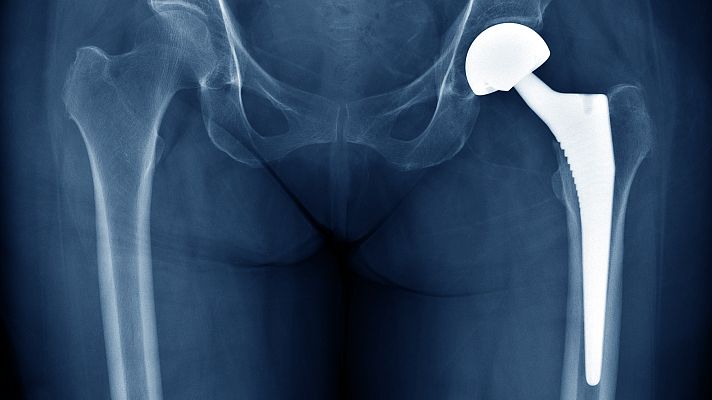

La Audiencia Nacional está investigando a la farmacéutica estadounidense Johnson & Johnson por comercializar presuntamente prótesis de cadera defectuosas que han sido implantadas en varios países, entre ellos España, donde hay 1.471 afectados. Las prótesis, que dejaron de implantarse hace nueve años por riesgo para la salud de los enfermos, se distribuyeron en 70 hospitales.